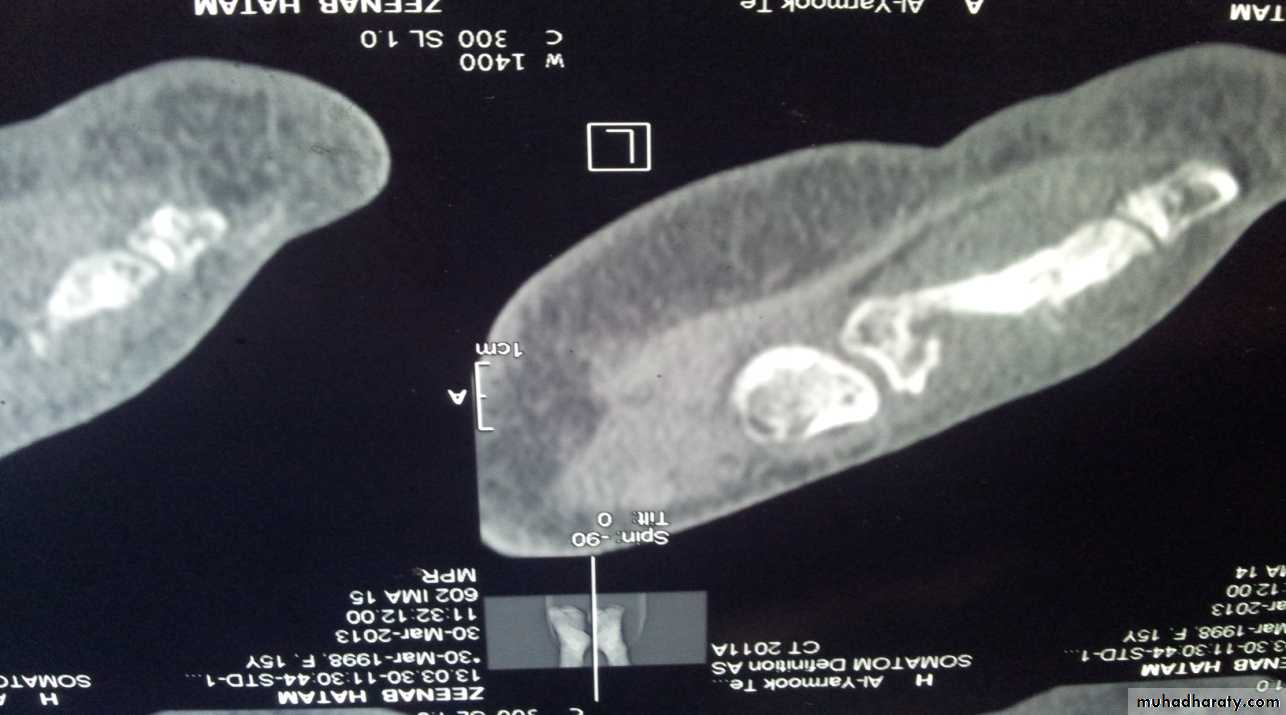

Imaging:

X-Ray: shows area of rarefaction surrounded by sclerosis.

And sometimes with sequestra.

Sinogram helpful to localize the site.

Bone scan: useful for revealing hidden foci of infection.